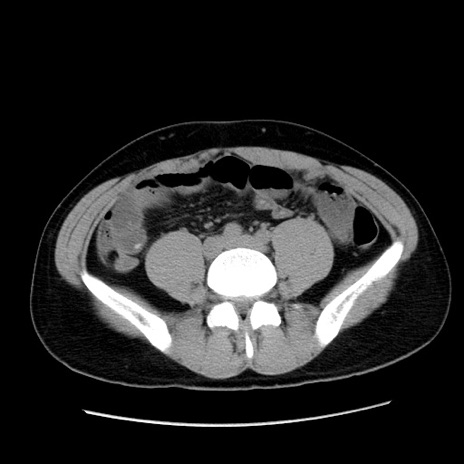

症例36(横断像)

冠状断像

【症例】20歳代 男性

【主訴】心窩部痛

【現病歴】今朝より上腹部痛あり。一旦軽快していたが再度出現したため救急要請。昨日夕に白身の魚を含む刺身を食べた。

【身体所見】BP 136/89mmHg、HR 74/min、BT 37.0℃、腹部:膨満、軟、心窩部に圧痛あり。反跳痛なし、筋性防御なし、腸雑音やや亢進あり。

【データ】WBC 17700、CRP 0.48